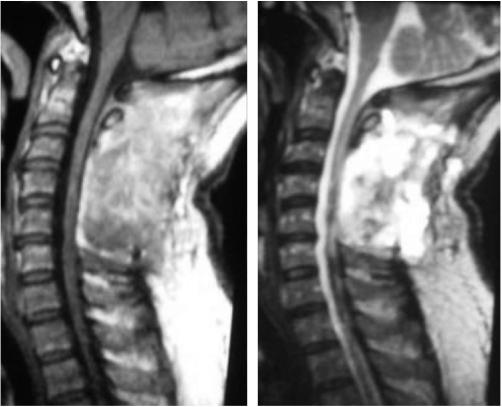

Intramedullary schwannomas unrelated with neurofibromatosis are uncommon tumors, but if correctly diagnosed and properly treated they may have a good prognosis.They have a wide range of clinical presentations, commonly presenting as a slowly progressive motor or sensory syndrome. We present a case report of a patient without neurofibromatosis with a surgically treated cervical intramedullary schwannoma.

与神经纤维瘤病无关的髓内神经鞘瘤是罕见肿瘤,但如果正确诊断并得到恰当治疗,其预后可能良好。它们有广泛的临床表现,通常表现为缓慢进展的运动或感觉综合征。我们报告一例无神经纤维瘤病患者的经手术治疗的颈髓内神经鞘瘤病例。